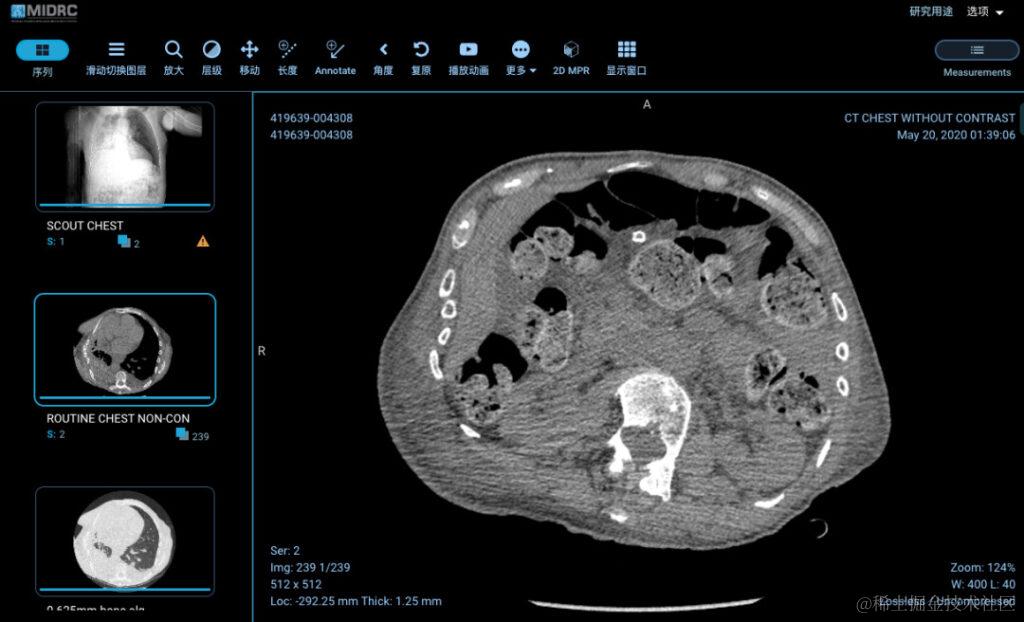

• 美国国立卫生研究院 (NIH): 赞助了若干知识库,如新冠肺炎相关医学影像和数据的开放获取平台 MIDRC,收集神经和脑成像的 IDA, NITRC-IR, FITBIR, OpenNeuro 和 NDA,癌症影像数据库 TCIA 和 IDC(其中 TCIA 在本地提供图像,IDC 在癌症研究数据共享云环境中提供图像);

图 5:MIDRC 数据库内一位 79 岁患者的胸部 CT